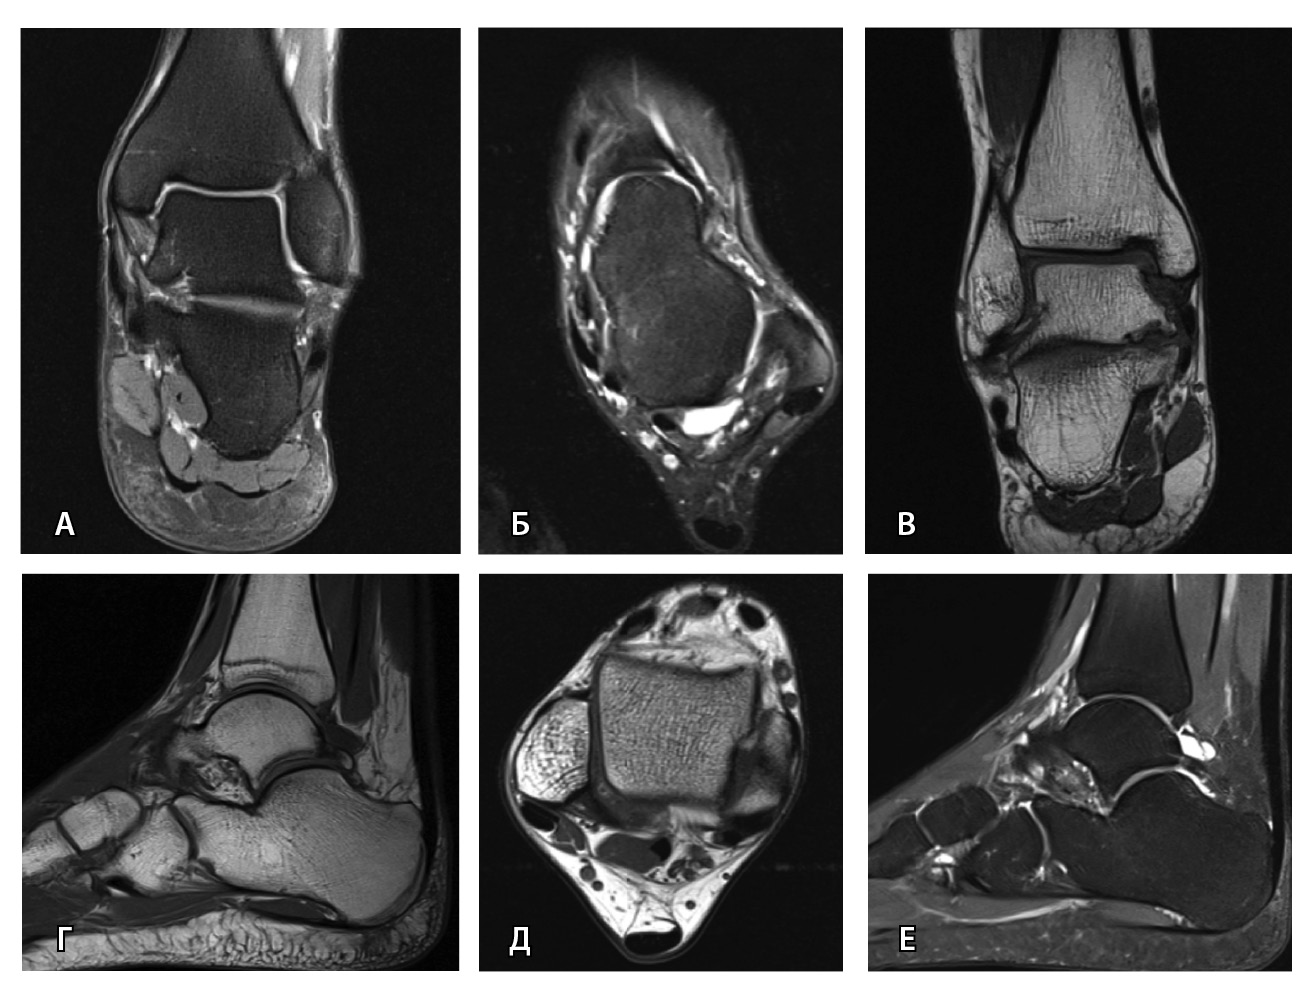

Переломы без смещения фрагментов, а также краевые и авульсионные переломы не всегда четко визуализируются на рентгенограммах из-за суперпозиции теней, наличия фиксирующих шин и гипсовых повязок, которые накладываются на зону интереса. При клинических признаках перелома и рентгеннегативной картине у таких пациентов КТ имеет большую диагностическую значимость (рис. 2).

Рис. 2. Рентгеннегативный перелом дистального метадиафиза большеберцовой кости 2-го типа по Солтеру – Харрису (стрелки) у мальчика 11 лет: А, Б – рентгенография; В – компьютерная томография (КТ), корональная плоскость; Г – КТ, сагиттальная плоскость; Д – КТ, аксиальная плоскость